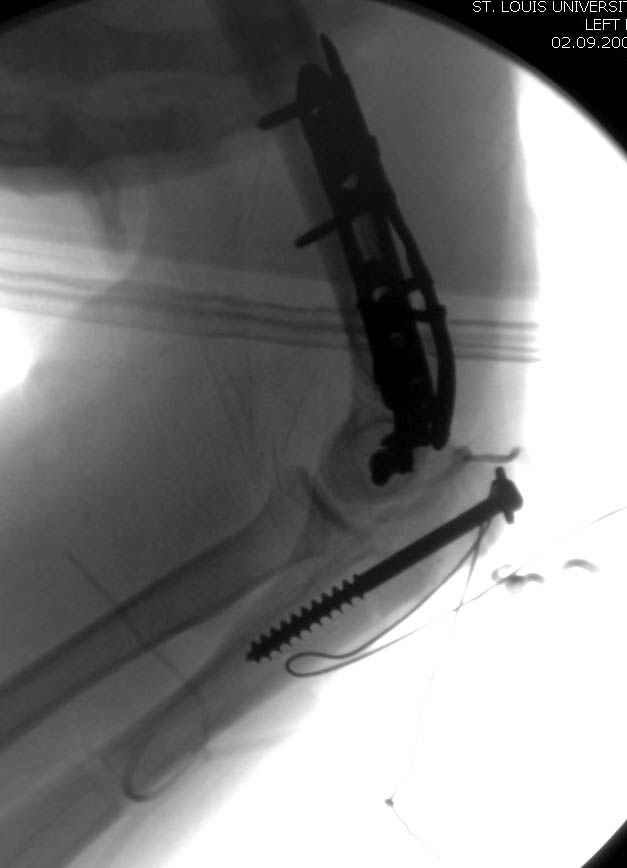

Примерный случай, только перелом был открытый, в задне-медиальной стороне рана около 2 см по характеру "изнутри кнаружи", неврологический статус со слабостью сгибания мизинца, также слабая абдукция и аддукция указательного пальца и сгибания в кисти.

Больному сделали обработку и наложили временный аппарат внешной фиксации плечо-предплечье.

На шестой день сделали открытую репозицию чрезлоктевым доступом двумя locking plate, локтевой нерв был ушибленным, после операции положительная динамика в Flexor Carpi Ulnaris. Фиксацию локтевого отростка произвели tension band technique с дополнительным шурупом.

Этапы операции на снимках....